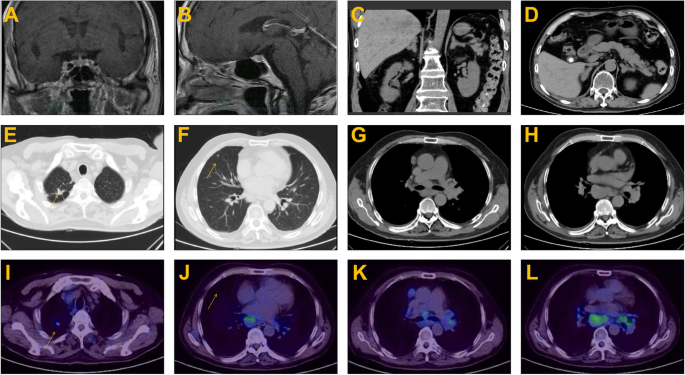

The results of the laboratory test on admission and the function of the endocrine glands are summarized in Tables 1 and 2. Urinary potassium excretion was inappropriately increased (Table 1). The serum cortisol level was increased, and diurnal rhythm was lost. The level of serum cortisol at 8 am was > 50 µg/dL after the low-dose dexamethasone suppression test(LDDST), and the patient was diagnosed with CS. ACTH dependency was confirmed based on remarkably elevated ACTH levels (Table 2). Pituitary MR was normal (Fig. 1a and b). The serum cortisol level at 8 am before and after the high-dose dexamethasone suppression test (HDDST) was 212 µg/dL and 208 µg/dL (calculated with the measured value and dilution rate), respectively (Table 2). Although the above results strongly suggested EAS, bilateral inferior petrosal sinus sampling (BIPSS) was routinely arranged for verification, mainly for two reasons. First, false positive and false negative results occur in both HDDST and regular imaging(pituitary MR and chest CT). For example, the HDDST results for EAS and CD sometimes overlap. Some patients with EAS have coexisting pituitary adenomas that are not the source of ACTH. Second, in very few patients, CD is caused by hyperplasia instead of adenoma, resulting in a negative finding on pituitary MR. Then, BIPSS was successfully performed (PRLleft/PRLperipheral and PRLright/PRLperipheral were 4.3 ± 0.5 and 2.5 ± 0.3, respectively). The left, right and peripheral ACTH levels were 789.9 ± 5.2 pg/mL, 773.6 ± 18.2 pg/mL and 726.5 ± 26.7 pg/mL (three samples for each), respectively, and the left, right and peripheral ACTH/PRL levels were 12.4 ± 1.4, 21.4 ± 2.4 and 49.1 ± 2.2, respectively. The diagnosis of EAS was made based on the HDDST and BIPSS results. Chest and abdominal CT as well as neck ultrasound were further arranged. Abdominal CT showed diffuse enlargement of the bilateral adrenal glands (Fig. 1c and d), and there were no abnormalities in the pancreas. Chest CT indicated two nodules in the superior and middle lobes of the right lung (Fig. 1e f) and prominent mediastinal lymphadenopathy (Fig. 1g h). Elevated tumour biomarkers, including carcinoembryonic antigen (CEA), cytokeratin 21 − 1 fragment CYFRA21-1 and neuron-specific enolase(NSE), were detected (Table 1). Thyroid ultrasound showed no abnormality. 68Ga-PET/CT suggested high-density opacity in the superior lobe of the right lung with a slight abnormally increased uptake of 68Ga-DOTA-NOC, fitting the characteristics of chronic infection (Fig. 1i). The high-density nodule in the middle lobe of the right lung was found without abnormal uptake of 68Ga-DOTA-NOC (Fig. 1j). Multiple lymph nodes in the left supraclavicular fossa, right root of the neck, mediastinum and bilateral hili of the lung were found partially fused into a mass with abnormal uptake of 68Ga-DOTA-NOC (Fig. 1k and l). Considering that the lymph nodes in the supraclavicular fossa and root of the neck might be distant metastases which is differ from the primary lesion, lymph nodes in the mediastinum and bilateral hili were preferable for biopsy. Therefore, mediastinoscopic lymph node biopsy was performed. The lymph nodes were pale and friable (Fig. 2a). The pathological diagnosis was small-cell and large-cell neuroendocrine carcinoma (LCNEC)according to the 2018 World Health Organization expert consensus proposal on the classification framework for neuroendocrine neoplasms [3] (Fig. 2b and c). Mitosis was approximately 80/10 HPF (Fig. 2d), and the Ki-67 index was 80 % (Fig. 2e). ACTH staining was positive (Fig. 2f).

Imaging examinations. Pituitary MRI revealed no abnormalities (a and b). Abdominal CT showed diffuse enlargement of the bilateral adrenal glands (c and d). Chest CT indicated two nodules in the superior (e) and middle lobes of the right lung (f) and mediastinal lymphadenopathy (g and h). 68Ga PET/CT demonstrated high-density opacity in the superior lobe of the right lung with a slight abnormally increased uptake of 68Ga-DOTA-NOC (i). High-density nodules in the middle lobe of the right lung did not show abnormal uptake of 68Ga-DOTA-NOC (j, arrow). Multiple lymph nodes in the mediastinum and bilateral hili of the lung partially fused into a mass with abnormally increased uptake of 68Ga-DOTA-NOC (k and l)